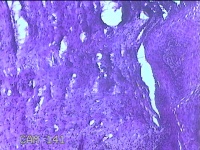

性别

女

年龄

54岁

临床诊断

宫颈上皮内瘤变Ⅰ级

一般病史

反复阴道脱出肿物3年余。

标本名称

宫颈组织

大体所见

灰白暗红色组织4.8x1.5x0.3cm一块,肥大,糜烂,切面灰白粉红色,质软

图2